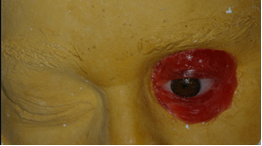

Consideraciones quirúrgicas generales: Los tres principales sitios de colocación de implantes extra-orales, según B. Badie12 son: la región temporal, la región óculo-palpebral y la región naso-maxilar. En la región óculo-palpebral se utiliza generalmente, el reborde supraorbitario, que permiten la colocación de implantes de 3-4 milímetros de largo. A veces es posible colocar implantes más largos, dependiendo de una previa evaluación radiológica. El índice de éxito en esta región, es menor que para la región del temporal, por el poco espesor del reborde y por la baja densidad ósea. Es recomendable utilizar implantes sin plataforma expandida en esta región, ya que existe gran riesgo de exposición, por el hecho de ser un hueso fino. El cirujano tiene que tener mucho cuidado para no perjudicar la estética de la ceja en el momento de reposicionar el colgajo2. De acuerdo a lo mencionado anteriormente, surge la idea de utilizar implantes dentales para esta región. Actualmente presentan características en su diseño que los hacen más indicados, se dispone de implantes de menor diámetro, cónicos y con roscas más agresivas para compensar la baja densidad ósea, consiguiendo una buena estabilidad primaria (Fig. 3).

Para obtener un buen resultado protésico, y mantener un buen estado de salud del tejido peri-implantar, es fundamental realizar una correcta técnica quirúrgica. La manipulación de los tejidos blandos deberá ser la adecuada. Se debe dejar con anterioridad, una región alrededor de los implantes sin folículos pilosos. También se debe remover tejido subcutáneo, en una extensión de 10 milímetros aproximadamente alrededor de los implantes13. Por lo tanto, el tejido peri-implantar ideal deberá ser fino, inmóvil, sin folículos pilosos y sin escalones14. Los posibles sitios de implantación en esta región son: el borde superior, lateral e inferior de la órbita, donde pueden ser colocados implantes de 3-4 milímetros de largo, como ya fue mencionado anteriormente. Un mínimo de 3 o 4 implantes son necesarios para estas prótesis. El eje longitudinal del implante deberá estar dirigido hacia el centro de la órbita. Una guía quirúrgica será fundamental para dar la información sobre la posición de los implantes, para que éstos no interfieran con la posición de la prótesis ocular. Los pilares trans-epiteliales deben quedar por dentro de los límites de la cavidad orbitaria, para no perjudicar la prótesis. Es fundamental, el uso de guías quirúrgicas (Fig. 2), y la presencia del rehabilitador en el acto de la cirugía2.

Medicación y atención post-operatoria. La paciente recibió 875 mg de amoxicilina por vía oral cada 12 horas durante 7 días. Para la analgesia, se prescribe ibuprofeno 600 mg por vía oral cada 8 horas durante 3 días. La evaluación postoperatoria tuvo lugar siete días después de la cirugía cuando se retiran las suturas y las gasas, y mensualmente hasta 4-6 meses. Después de este período, se evaluó la oseointegración de los implantes y se realizó la prótesis (Fig. 5). Los criterios utilizados para evaluar la oseointgración son: ausencia de dolor, disestesia e inmovilidad15